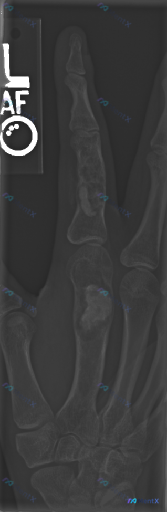

左手食指斜位片见爆米花样钙化,这个病灶更像内生软骨瘤还是低级别软骨肉瘤?

网上看到一张左手食指斜位的X光片,病灶的影像学表现有点意思,整理出来和大家讨论。

- 食指近节指骨:骨髓腔内见多处类圆形、斑片状高密度钙化影,呈「爆米花样」改变,骨皮质轻度膨胀变薄

- 第二掌骨:干骺端至骨干区域有明显溶骨性破坏区,内见团块状、边界尚清的高密度钙化影

- 未见明确急性外伤性骨折线,关节间隙尚可,无明显脱位

- 局部软组织无明显广泛肿胀,未见异物影

目前的争议点在于:这个「爆米花样钙化+膨胀性骨质破坏」的组合,到底更偏向良性的内生软骨瘤,还是必须优先警惕的低级别软骨肉瘤?